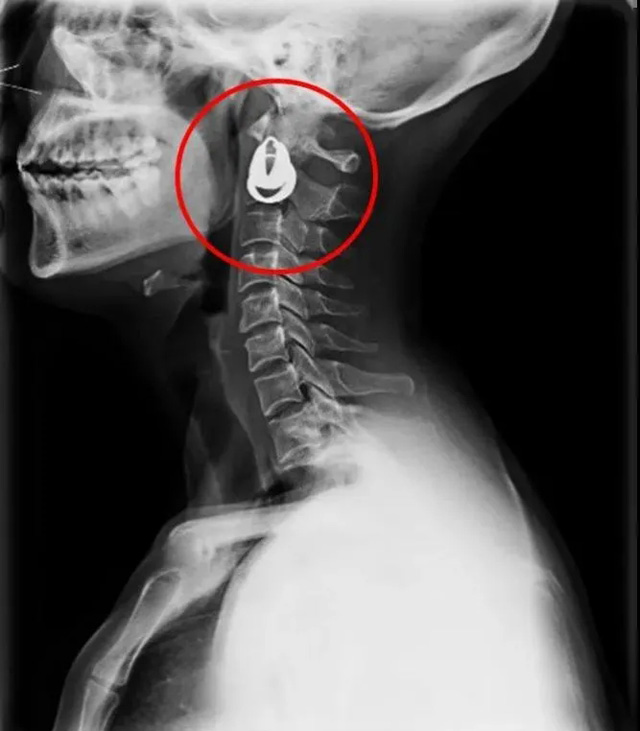

DR是一種比較常規(guī)的基礎(chǔ)影像學(xué)檢查方式,適用于人體各部位的健康普查及疾病檢查等優(yōu)勢(shì),在臨床基礎(chǔ)檢查中備受醫(yī)生和患者的青睞。DR體檢車在健康體檢中有著非常重要的地位,由通過電纜串接在一起的探測(cè)板、掃描控制器、系統(tǒng)控制及影像顯示器等構(gòu)成。對(duì)比CT檢查而言,DR檢查的價(jià)格更低,輻射劑量更小它可以讓疾病預(yù)防,微細(xì)病變可更好顯示診斷治療提供科學(xué)的結(jié)果依據(jù)。很多外傷患者都要做DR檢查,來判斷是否骨折或其他的情況。體檢過程中面對(duì)DR體檢車做檢查時(shí)候需要準(zhǔn)備注意什么呢?很多時(shí)候大家都有這樣的疑問,身上攜帶的物品是否會(huì)對(duì)圖像造成遮擋或給機(jī)器帶來干擾?檢查前如何準(zhǔn)備才不會(huì)影響檢查準(zhǔn)確性?

首先需要穿比較寬松的衣物,不要戴金屬的飾品。還可以用醫(yī)院的衣服,胸圍的也要脫掉,因?yàn)橛袖撊?。不然的話這些金屬飾品會(huì)干擾檢查圖像的清晰度,引發(fā)誤診或者漏診。半年內(nèi)需要備孕懷孕的人士,應(yīng)慎重或盡量避免放射線照射就需要跟醫(yī)生講,幼兒、年老體弱、危重患者,家屬應(yīng)有效配合醫(yī)生完成檢查;對(duì)不用檢查的部位做好防護(hù)工作。在DR已經(jīng)開始運(yùn)作時(shí)候,檢查進(jìn)行中的提示燈亮了,不要推開檢查室大門跟勿隨意進(jìn)入,不然會(huì)受到輻射。按照醫(yī)生的要求保持好體位。曝光時(shí)候不動(dòng)平靜均勻呼吸時(shí)屏氣,避免產(chǎn)生運(yùn)動(dòng)偽影這樣才能保障圖像的高清準(zhǔn)確。